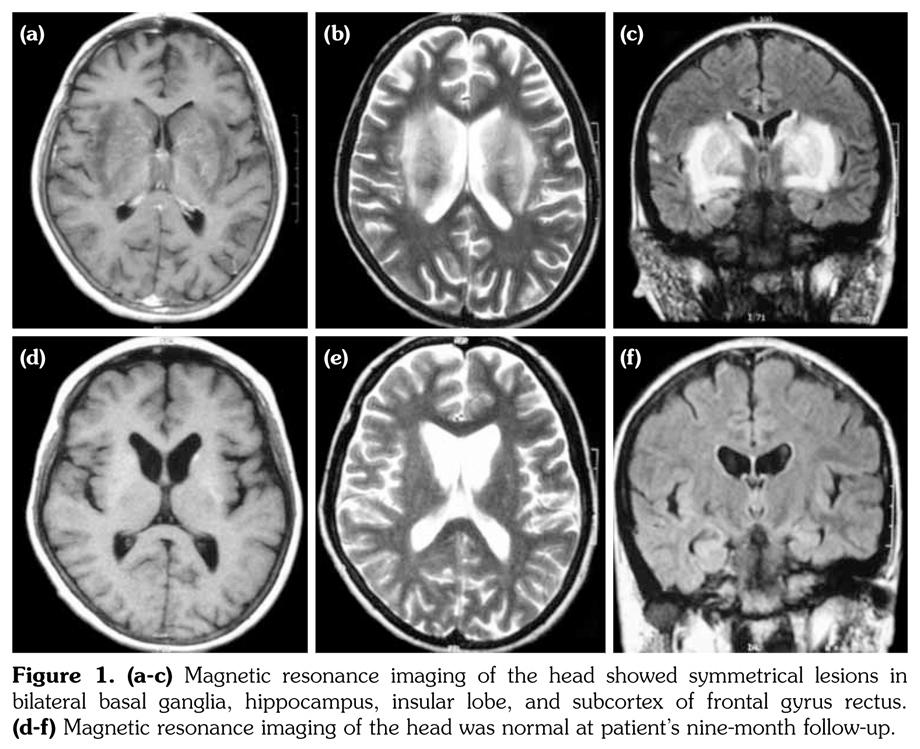

Head magnetic resonance imaging showed symmetrical long T1 signal, slight long T2 signal, and high T2 flair signal in bilateral basal ganglia, hippocampus, insular lobe, and subcortex of frontal gyrus rectus. Bilateral external capsule showed long T1 signal, long T2 signal, and high T2 flair signal (Figure 1). Enhanced magnetic resonance imaging showed a slightly increased signal intensity of bilateral basal ganglia. Lumbar puncture showed that the cerebrospinal fluid (CSF) was colorless and transparent with CSF pressure at 120 mmH2O. Biochemical test of CSF showed normal levels of protein (175 mg/L), glucose (3.1 mmol/L), lactate dehydrogenase, chloride, and adenosine deaminase, but a slight elevation of white blood cells (25*106)/L). CSF smear, culture, Gram staining, acid-fast staining, tuberculosis DNA, virus antibody test, and fungal test were all negative. Autoantibodies to dsDNA and ribosomal P protein were positive in the CSF, but anti-phospholipid, anti-beta2GP1, anti- neuronal, anti-glial fibrillary acidic protein, anti- endothelial cell, and anti-N-methyl-D-aspartate antibodies were negative. Since none of the drugs administered appeared to have potential side effect of parkinsonism and no other causes of parkinsonism could be recognized for this particular patient, she was considered to have NPSLE.

High dose intravenous methylprednisolone (500 mg/day) was prescribed for three days followed by oral prednisolone (1 mg/kg/day), and intravenous cyclophosphamide (600 mg/m2 body surface area) was prescribed once. Intrathecal injection of methotrexate (MTX) (10 mg) and dexamethasone (DXM) (10 mg) were applied once a week for two weeks. After these treatments, the patient showed steady improvements in her gait, speech and movements. Two weeks later, her blood showed normal level of complement 3 (0.84 g/L) and erythrocyte sedimentation rate (18 mm/h). She was discharged on maintenance of oral prednisolone (30 mg/day), oral hydroxychloroquine (200 mg/day), and intravenous cyclophosphamide (800 mg/month). At the patient’s two-month follow-up visit, we noticed that she had normal facial expression, speech, movement, and gait. Complement 3 (0.86 g/L) and erythrocyte sedimentation rate (12 mm/h) remained normal and the titer of antinuclear antibody decreased to 1:40. The Systemic Lupus Erythematosus Disease Activity Index was reevaluated with a score of 0. Patient was still in remission at nine-month follow-up, and her head magnetic resonance imaging was normal (Figure 1).